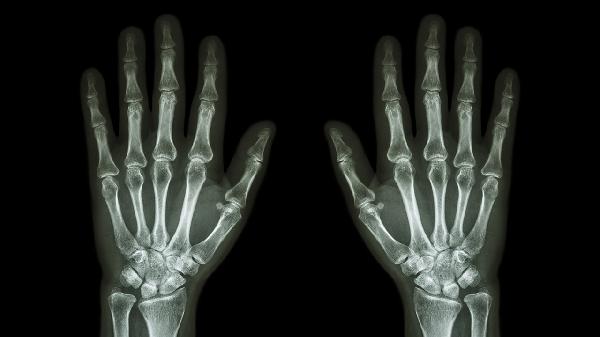

手指关节疼痛肿胀可通过热敷冷敷、药物治疗、物理治疗、调整饮食、手术治疗等方式缓解。手指关节疼痛肿胀可能与外伤、骨关节炎、类风湿关节炎、痛风性关节炎、感染性关节炎等因素有关。